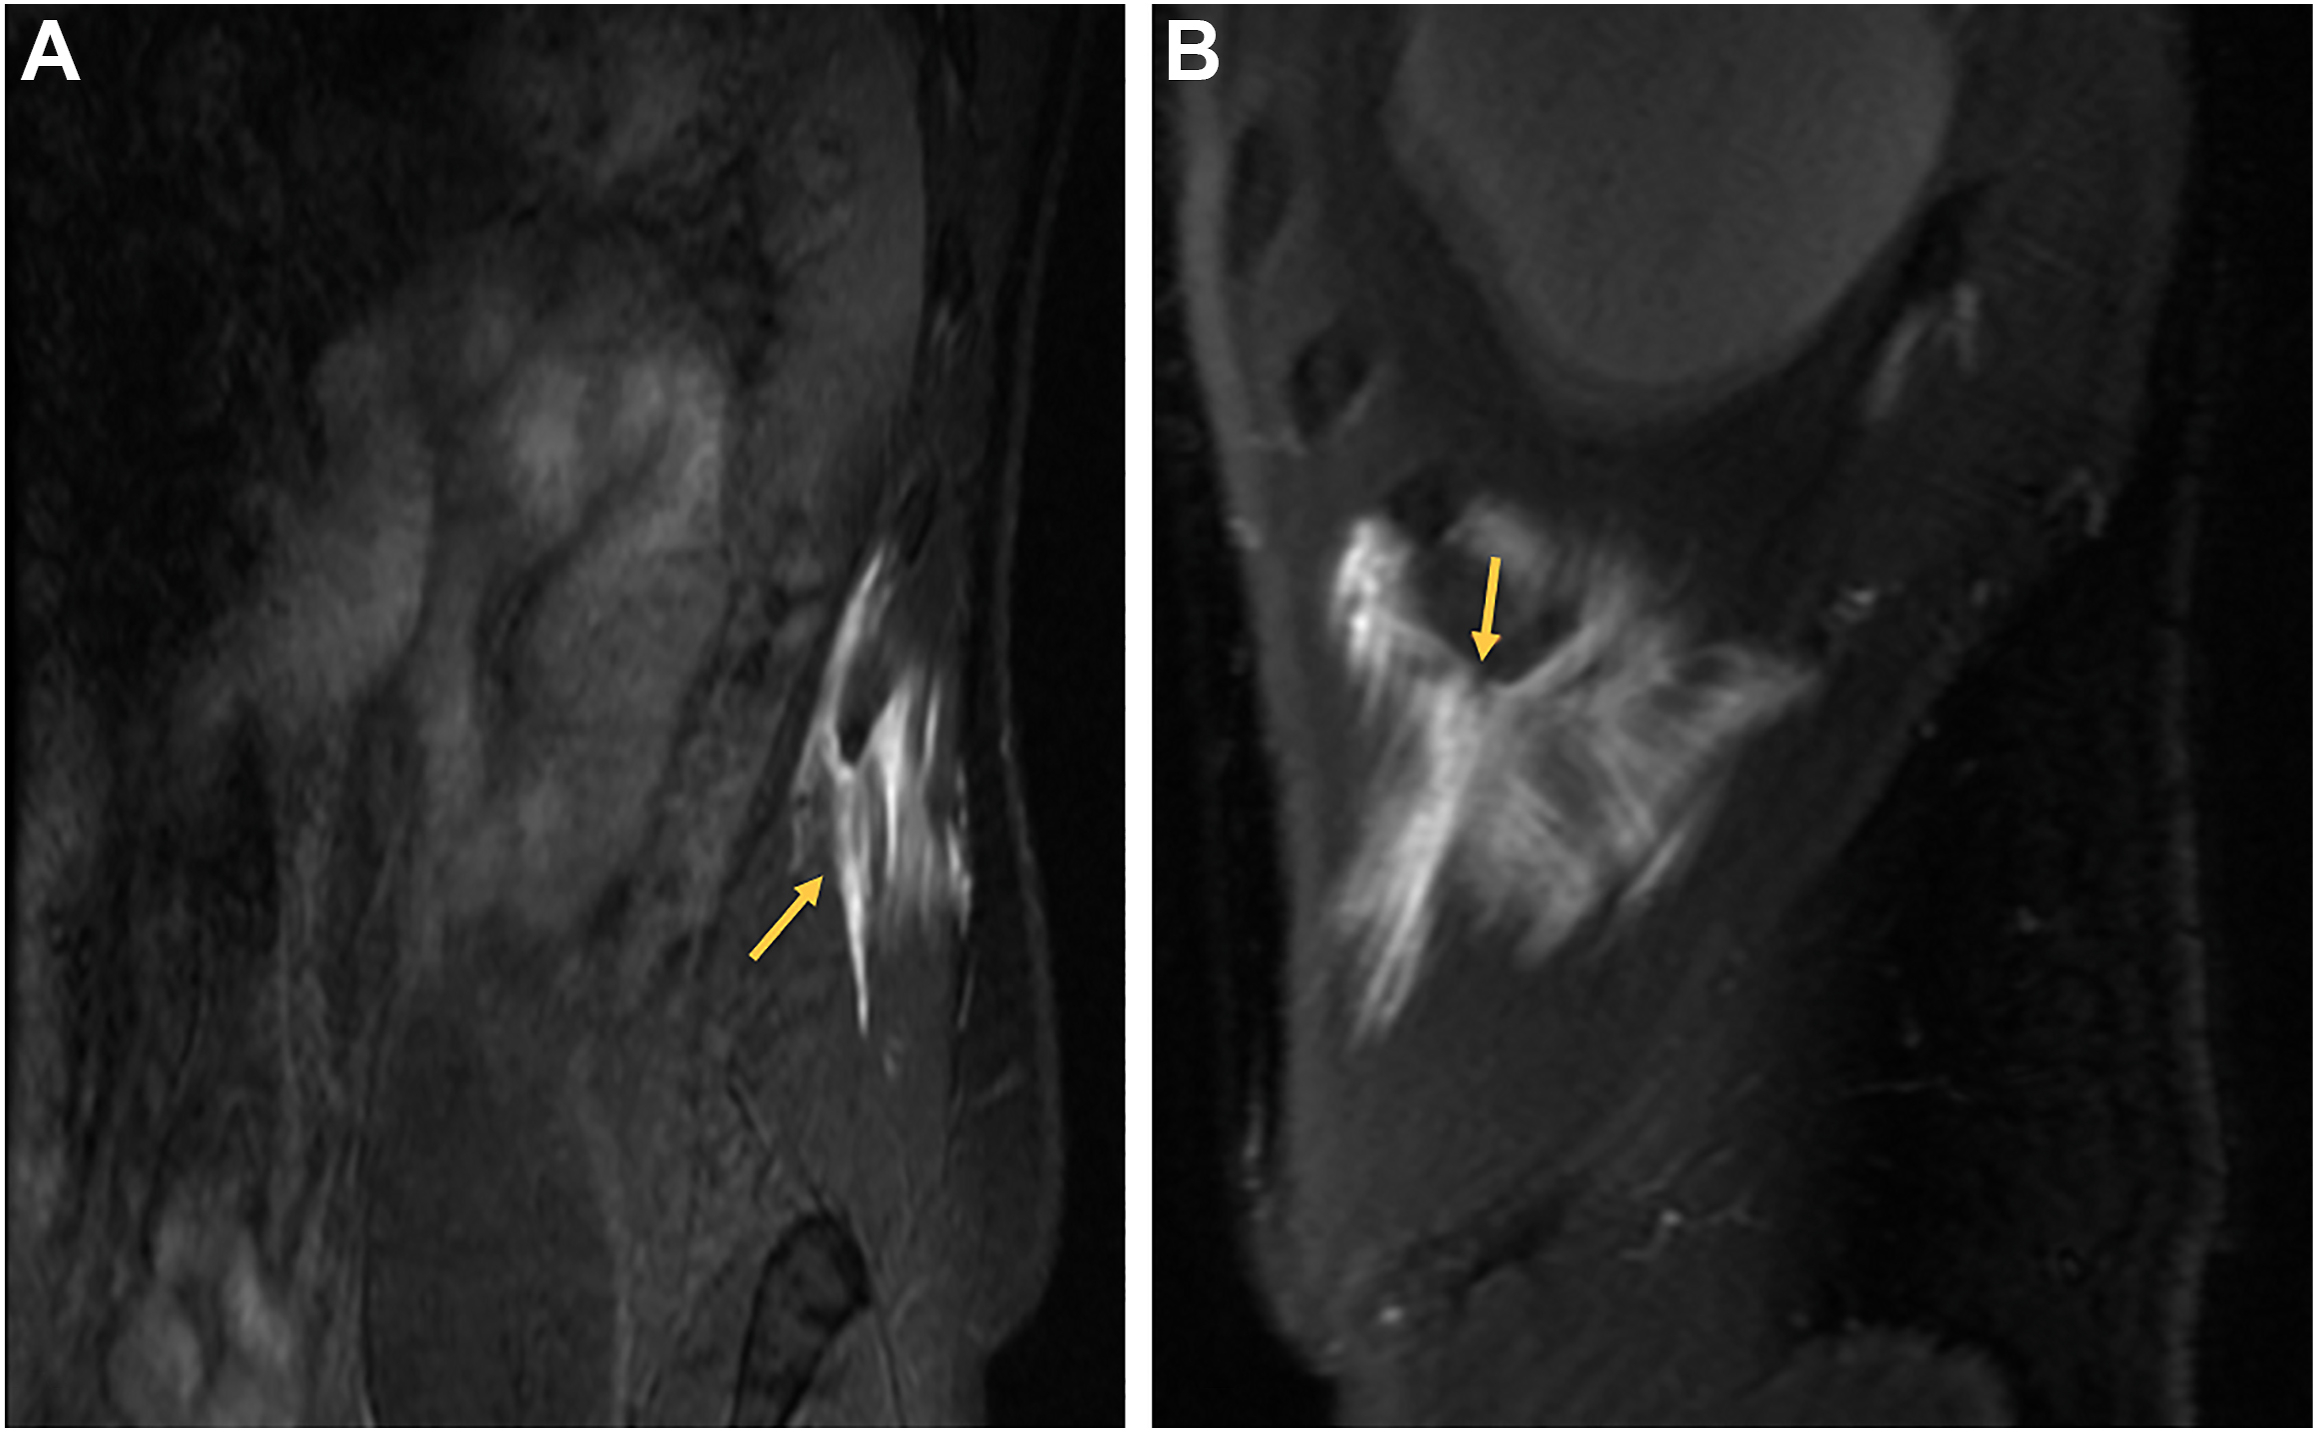

Core muscle strains

The abdominal core muscles, including the rectus abdominis, internal and external obliques, and intercostals, play an important role in pitching and hitting as proper abdominal muscle activation is crucial for generating optimal ball velocity and bat speed. Oblique muscle strains are currently the fifth most common injury in professional baseball resulting in an average of 21.4 days missed per injury ( Fig. 1 , Tables 1 and 2 ). Most are acute noncontact injuries resulting from throwing or batting with pitchers being the most affected. Most abdominal muscle injuries in pitchers are contralateral to their dominant throwing arm, while in position players, the injury is more likely to occur contralateral to their dominant batting side. A recent study found that pitchers missed 5 more days per oblique muscle injury in comparison to position players ( P <.001). Similarly, a separate study found that pitchers with abdominal muscle strains averaged 35.4 days on the injured list in comparison to 26.7 days for position players ( P <.01).